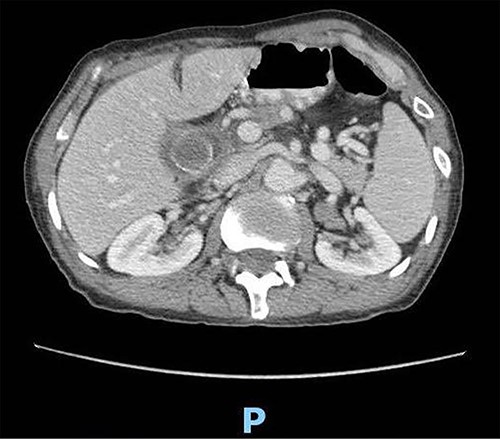

Upon clinical examination, the patient was vitally stable. Abdominal examination revealed a distended abdomen with generalized tenderness. Digital rectal examination revealed an empty rectum with no palpable masses. Laboratory investigations were unremarkable (Table 1). Abdominal X-ray was done (Fig. 2) and showed dilated large bowel loops suggestive of bowel obstruction. Enhanced CT scan of the abdomen and pelvis was obtained (Figs 3–5) and showed a dilated large bowel loop, with air fluid level. A 2.5-cm gallstone was noted, impacting the sigmoid colon and causing partial large bowel obstruction. There was evidence of pneumobilia with air foci within the gallbladder with a suspected fistula with the hepatic flexure.

Enhanced CT scan of the abdomen showing evidence of partial large bowel with pneumobilia, gallbladder seen with interrupted wall and suspected fistula with the hepatic flexure (axial view).